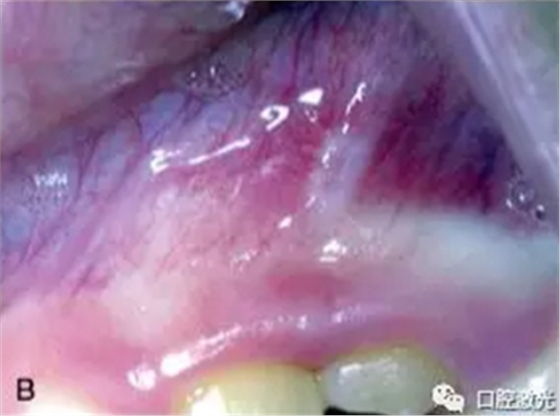

激光口腔潰瘍治療效果A:治療前,B:激光治療4天后

發(fā)生口腔潰瘍時(shí),灼痛是其突出特征,因此顧冠以“阿弗他”名(希臘文aphthous為“灼痛”之意),外觀為單個(gè)或者多個(gè)大小不一的2-4mm圓形或橢圓形潰瘍,表面覆蓋灰白或黃色假膜,中央凹陷,邊界清楚,周圍黏膜紅而微腫。具有周期性、復(fù)發(fā)性、自限性的特征,年齡不拘,發(fā)病年齡估計(jì)在10~20歲之間,女性較多。一年四季均能發(fā)生,能在10天左右自愈,目前病因目前尚未明確。